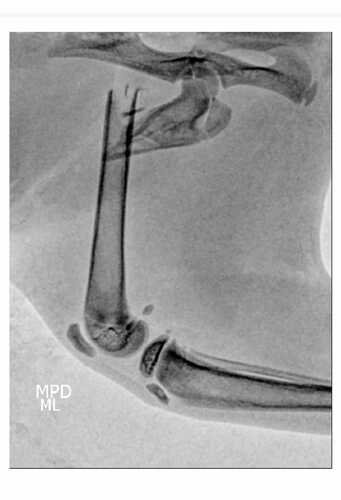

Olá sou a Gaia, tenho 3 meses adoro ronronar, sou muito dengosa e sapeca; no último domingo (04/02) fui atacada por um cachorro que entrou na minha casa, fui salva pelo meu dono e minha irmã canina, mas fui muito machucada, me levaram correndo para a tia veterinária que fez analgesia e um raio-x pra ver o que aconteceu com minha patinha e infelizmente ela foi quebrada, preciso de uma cirurgia para voltar a pentelhar todo mundo e infelizmente meu tutores não conseguem arcar com o valor; ficaria muito feliz com qualquer ajuda! Muito obrigada!